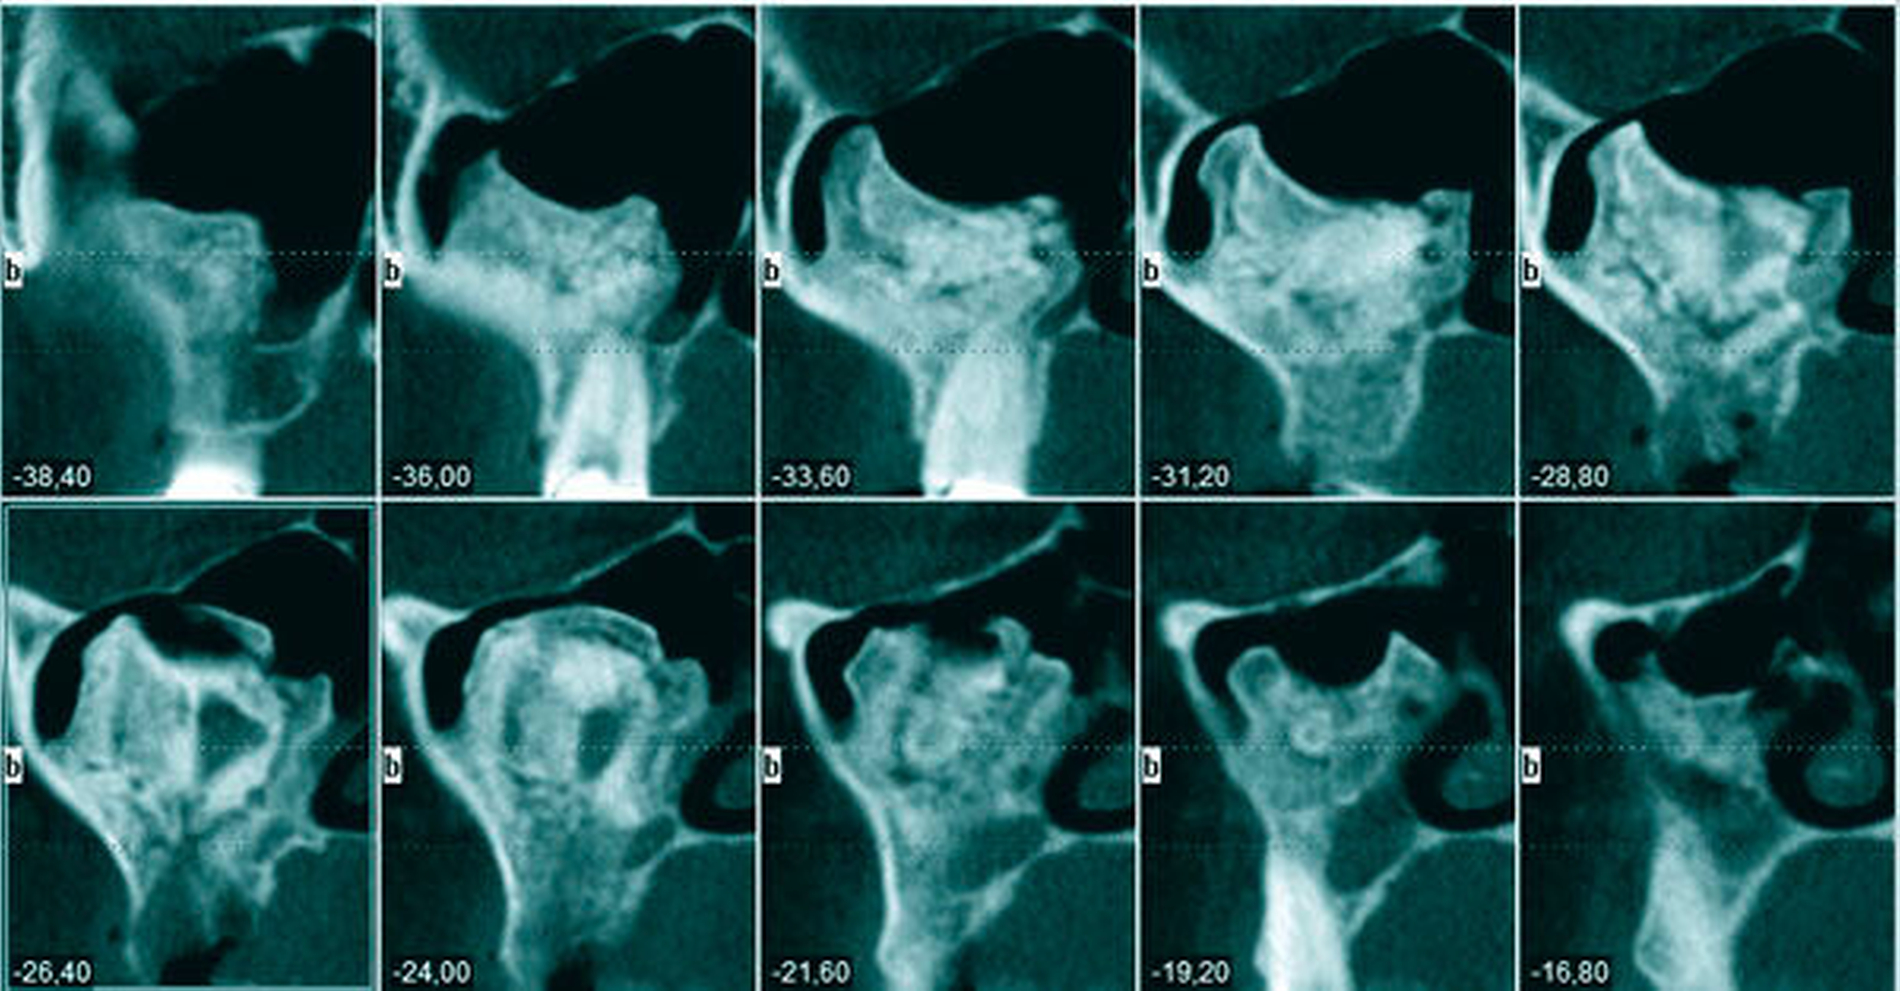

Eine 51-jährige Patientin wurde durch ihren Zahnarzt mit der Frage nach weiterführender Diagnostik an die Abteilung für Mund-, Kiefer, und plastische Gesichtschirurgie der Universität Mainz überwiesen. 14 Tage zuvor war die Frau mit einer rechtsseitigen Schwellung der Wange erwacht, woraufhin sie sich bei ihrem Hauszahnarzt vorstellte. Bei Vorliegen eines Fossa-canina-Abszesses wurde durch den Zahnarzt eine Inzision der Abszesshöhle und die Extraktion der schuldigen Zähne 14 und 16 durchgeführt. In der erstellten Panoramaschichtaufnahme (PAN) fiel ihm eine röntgendichte Raumforderung der rechten Kieferhöhle auf, die von der Universitätsmedizin untersucht werden sollte. Die Anamnese und die klinische Untersuchung zeigten sich unauffällig, so dass zwecks weiterer diagnostischer Analyse eine 3-D-Aufnahme (DVT) des Gesichtsschädels durchgeführt wurde (Abbildungen 1 bis 3).

Zur Diagnose und Evaluation empfiehlt sich eine dreidimensionale Darstellung des Befunds in Form einer DVT oder einer CT [Viswanatha, 2012; Lee et al., 2015; Celenk et al., 2012; Georgalas et al., 2011; Buyuklu et al., 2011], um die präzise Größe, Lokalisation und Binnenstruktur abschätzen wie auch eine differenzialdiagnostische Analyse infrage kommender Pathologien vornehmen zu können [Lee et al., 2015; Georgalas et al., 2011]. Typischerweise erscheint das Osteom als am umliegenden Knochen anliegende, umschriebene, dichte Masse. Umgebende Strukturen, insbesondere knöcherner Art, weisen keinerlei lytische Veränderungen auf. Lediglich größere Befunde können – wie im vorliegenden Fall – durch wachstumsbedingten Druck zu einer Ausdünnung und Verschiebung von Nachbarstrukturen führen [Viswanatha, 2012]. Radiologisch kann sich das Osteom der Kieferhöhle als gleichmäßige sklerotische Struktur, heterogene Matrix mit und ohne kortikale Schale oder mit laminiertem Muster darstellen [Lee et al., 2015; Earwaker, 1993; Janovic et al., 2013].